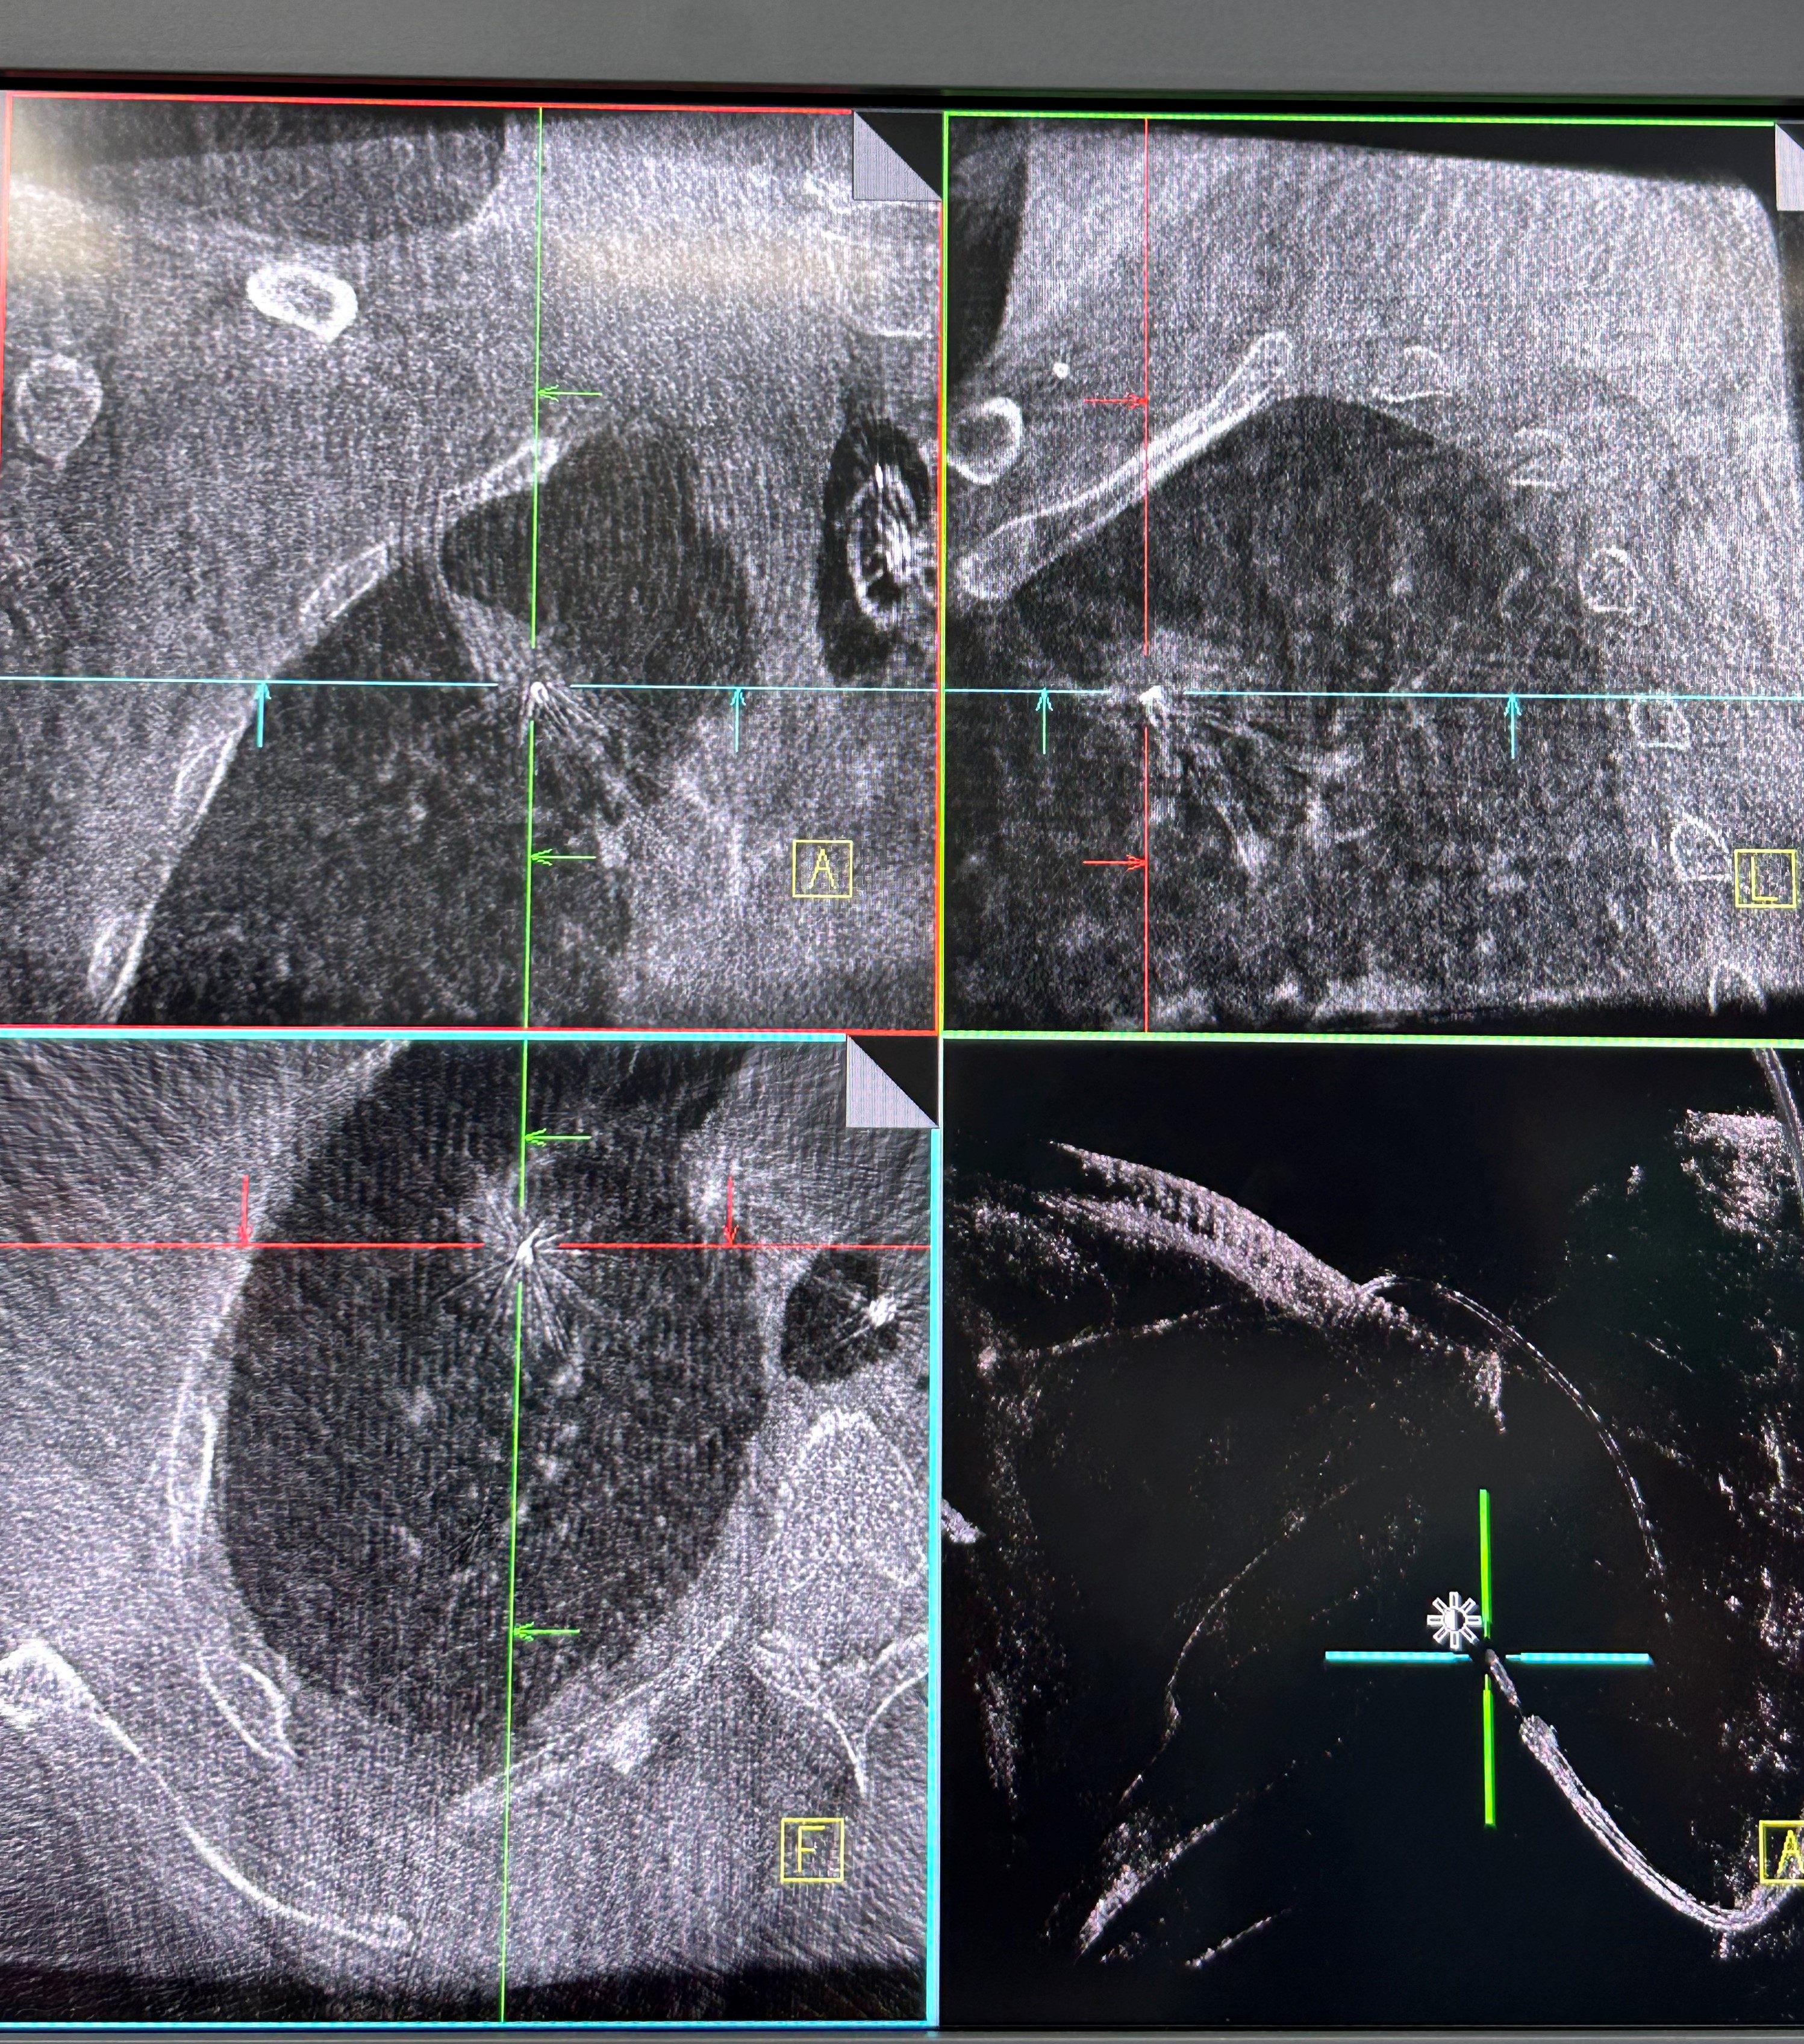

手术当日,呼吸科团队帮助患者在全麻下完成气管插管,手术由蒋军红主任指导,负责手术方案的实时优化与安全保障。曾大雄主任医师和王兰主任医师精准操作机器人支气管镜,在支气管镜导航机器人的精准引导下,通过AI三维重建、智能路径规划以及多模态信息融合,将支气管镜精准“引导”至右上叶尖段病灶处。随后,团队启动CBCT(锥形束计算机断层扫描)通过实时影像复核确认靶病灶,实现病灶“毫米级”精准锁定,彻底解决肺部病灶“找不到、找不准”的核心难题。机器人气管镜导航技术实现了从术前规划到术中操作全流程的智能精准控制,真正做到了肺部病灶的精准覆盖。

明确肿瘤诊断后,治疗方案即刻启动。团队经导航引导鞘管,精准插入一次性冷冻消融针(直径仅1.9mm)。再次通过CBCT确认消融针完全“扎根”于右上叶尖段病灶内后,开启冷冻治疗模式:以-160℃深低温冷冻10分钟、复温至45℃维持3分钟为一个治疗循环。完成了3次循环后,为确保病灶无遗漏,团队微调消融针位置,再次追加2次循环治疗。术后复查CBCT显示,病灶已呈现典型的冷冻后改变,术后两天复查胸部CT提示消融范围满意,治疗效果完全达到预期。整个手术过程中,患者生命体征始终平稳,术后第二天即可下床活动,真正实现了“微创治疗、快速恢复”的目标。

治疗前

治疗后